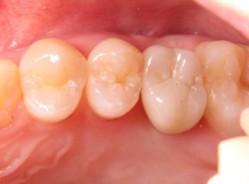

40代 女性

- リスク・副作用

- 術後疼痛、歯肉腫脹

- 治療の費用

- 合計¥686,000(税込)

【内訳】

インプラント(1本) ¥440,000

その他費用¥246,000

(薬・注射・レントゲン・CT・データ分析・骨造成・サージカルステント・血液検査) - 年齢/性別

- 40代/女性

- 患者の具体的な症状

- 左上6欠損のため義歯を使用していたが、噛むと痛みがあり不快なため、インプラント治療を希望

- 検査方法

- コーンビームCT、レントゲン撮影

- 診断結果

- 左下6欠損

- 治療詳細

- コーンビームCTによる画像診断で垂直的な骨高が不足し骨密度が少ないため、ソケットリフトによる骨再生治療とインプラント埋入を同時に行った。

- 通院回数

- 7回

- 治療期間

- 7か月